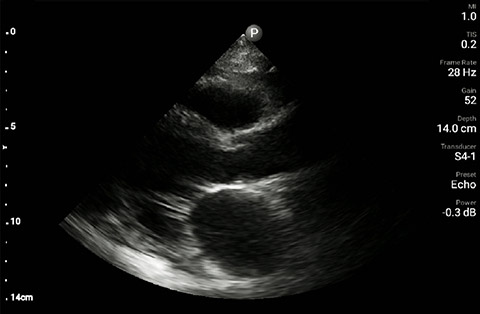

The patient had reduced LV systolic function without new or severe valvular pathology, a dilated, non-collapsing IVC, and diffuse B lines (left greater than right) on lung ultrasound imaging.

Parasternal long-axis